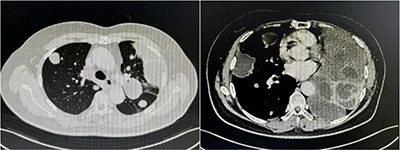

今年3月,潘某自觉胸闷气短,后来症状逐渐加重,体力下降明显,胸口仿佛有千斤巨石压迫一般不能忍受。患者再次复查胸部CT,发现左肺的平滑肌瘤较前明显增大,其中最大一处占据了胸腔三分之二,左肺体积压缩至正常的三分之一,且肺脏内布满了大小不一的平滑肌瘤。患者左肺功能严重受损,生命受到威胁,进行下一步治疗刻不容缓。此病例极为罕见,肺内病变复杂,手术处置困难,患者辗转就医多家医院,最后来到了我院胸外科。面对如此罕见复杂的特殊疾病,胸外科主任赵志龙毅然接收了患者。